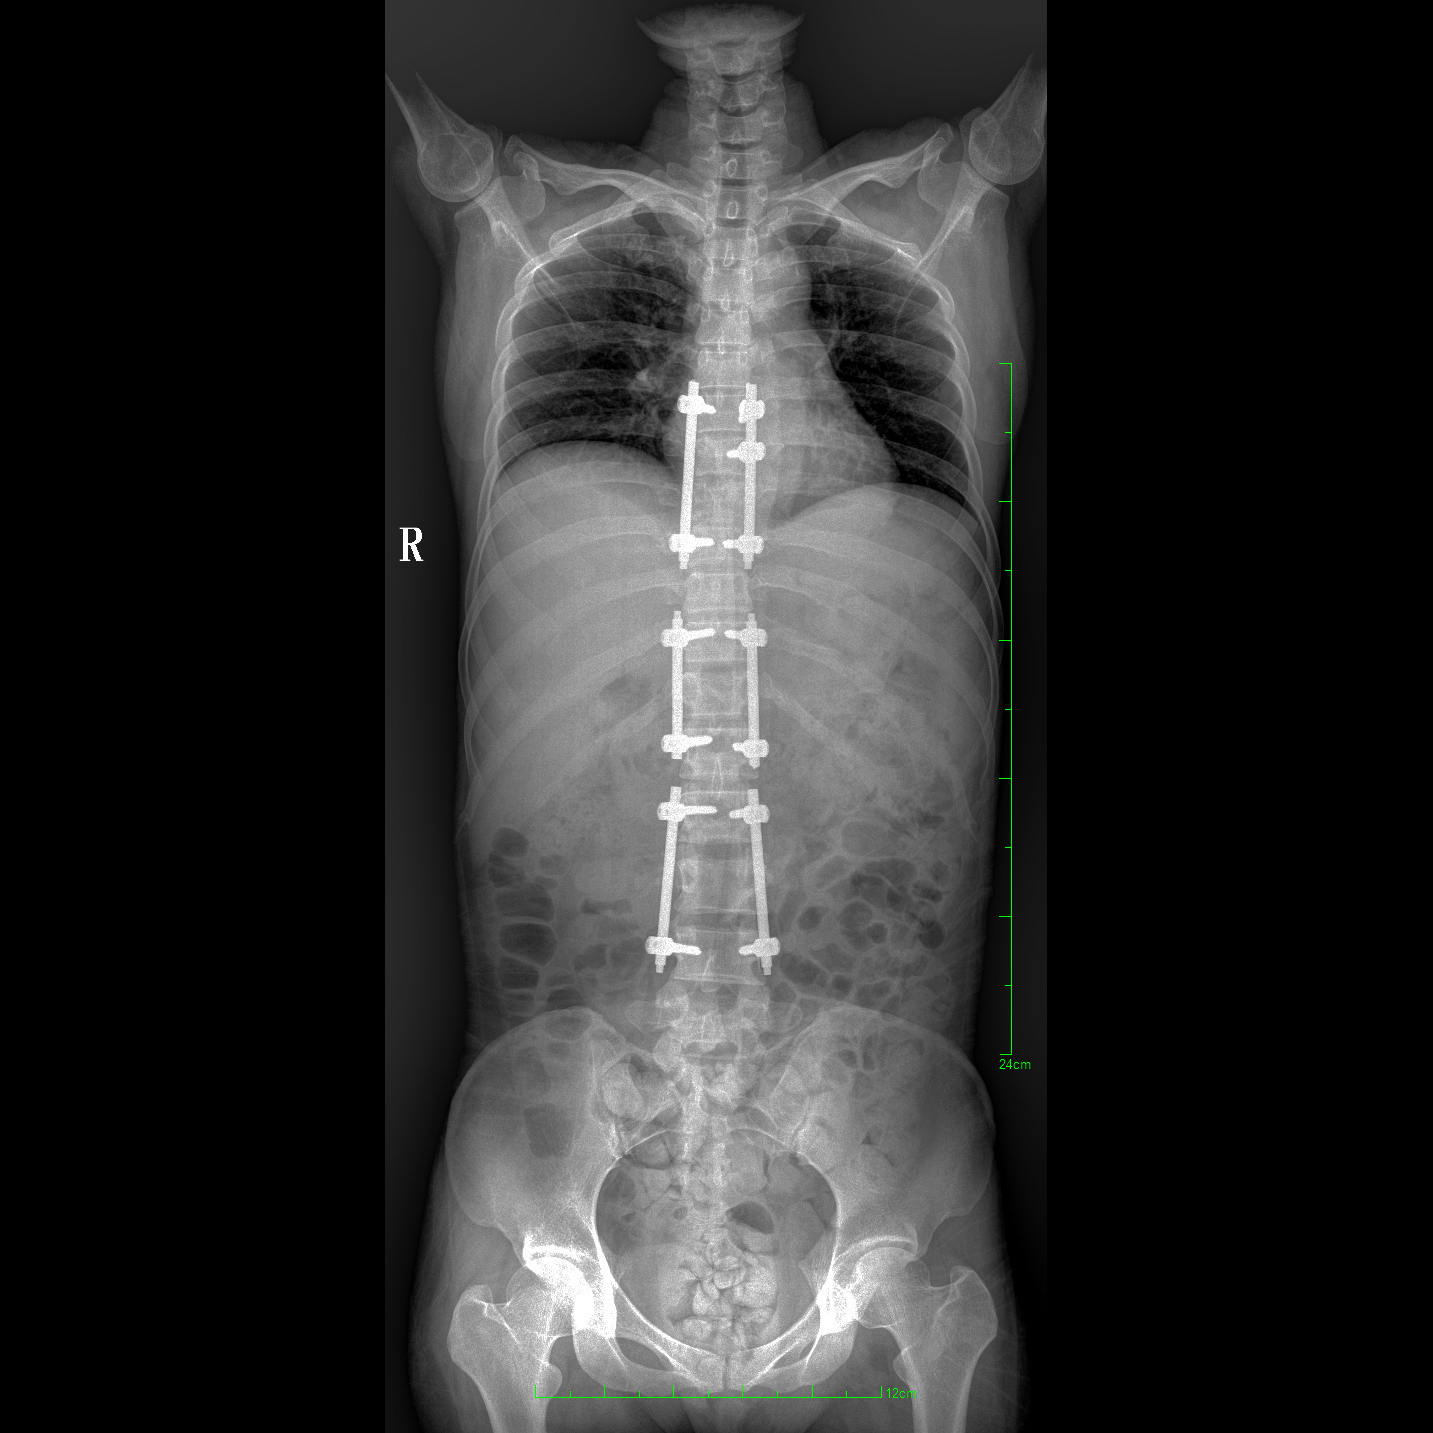

支持全脊柱攝影、雙下肢攝影、脊髓造影、復雜創(chuàng)傷、人工關節(jié)置換、關節(jié)損傷的修復重建等大視野臨床應用

17"*34"有效視野,一次成像不拼接。相較于多張攝影再軟件拼接的DR設備,PLX8600解決了拼接圖像存在密度不均勻,拼接處圖像配準和放大效應等問題,給臨床帶來了大視野影像解決方案,可一次性覆蓋全脊柱或雙下肢影像。

除常規(guī)靜態(tài)攝影外,PLX8600大平板具備動態(tài)透視和點片功能,透視采集功能可支持大視野、多角度的可視化觀察。通過可視化的動態(tài)影像,配合點片功能,能夠很好的觀察復雜部位病灶,有效的抓取關鍵幀,降低患者多次攝片的概率。如:全脊柱狀態(tài)評估、長骨關節(jié)活動度、下肢靜脈造影瓣膜功能評估、消化道功能評估、脊髓造影等更多大視野臨床應用。